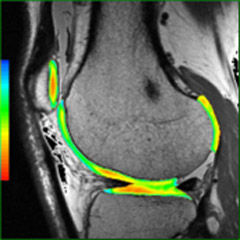

Mit der MRT können sowohl anatomische als auch physiologische Merkmale von Organen und Pathologien erkannt werden. Diese Vielseitigkeit macht die Bildgebungsmethode zu einem unverzichtbaren Diagnosewerkzeug. AW-Programme mit ihren vereinfachten Abläufen und intuitiver Benutzeroberfläche ermöglichen dem Anwender eine rasche und präzise Quantifizierung und qualitative Auswertung von MR-Untersuchungsergebnissen.